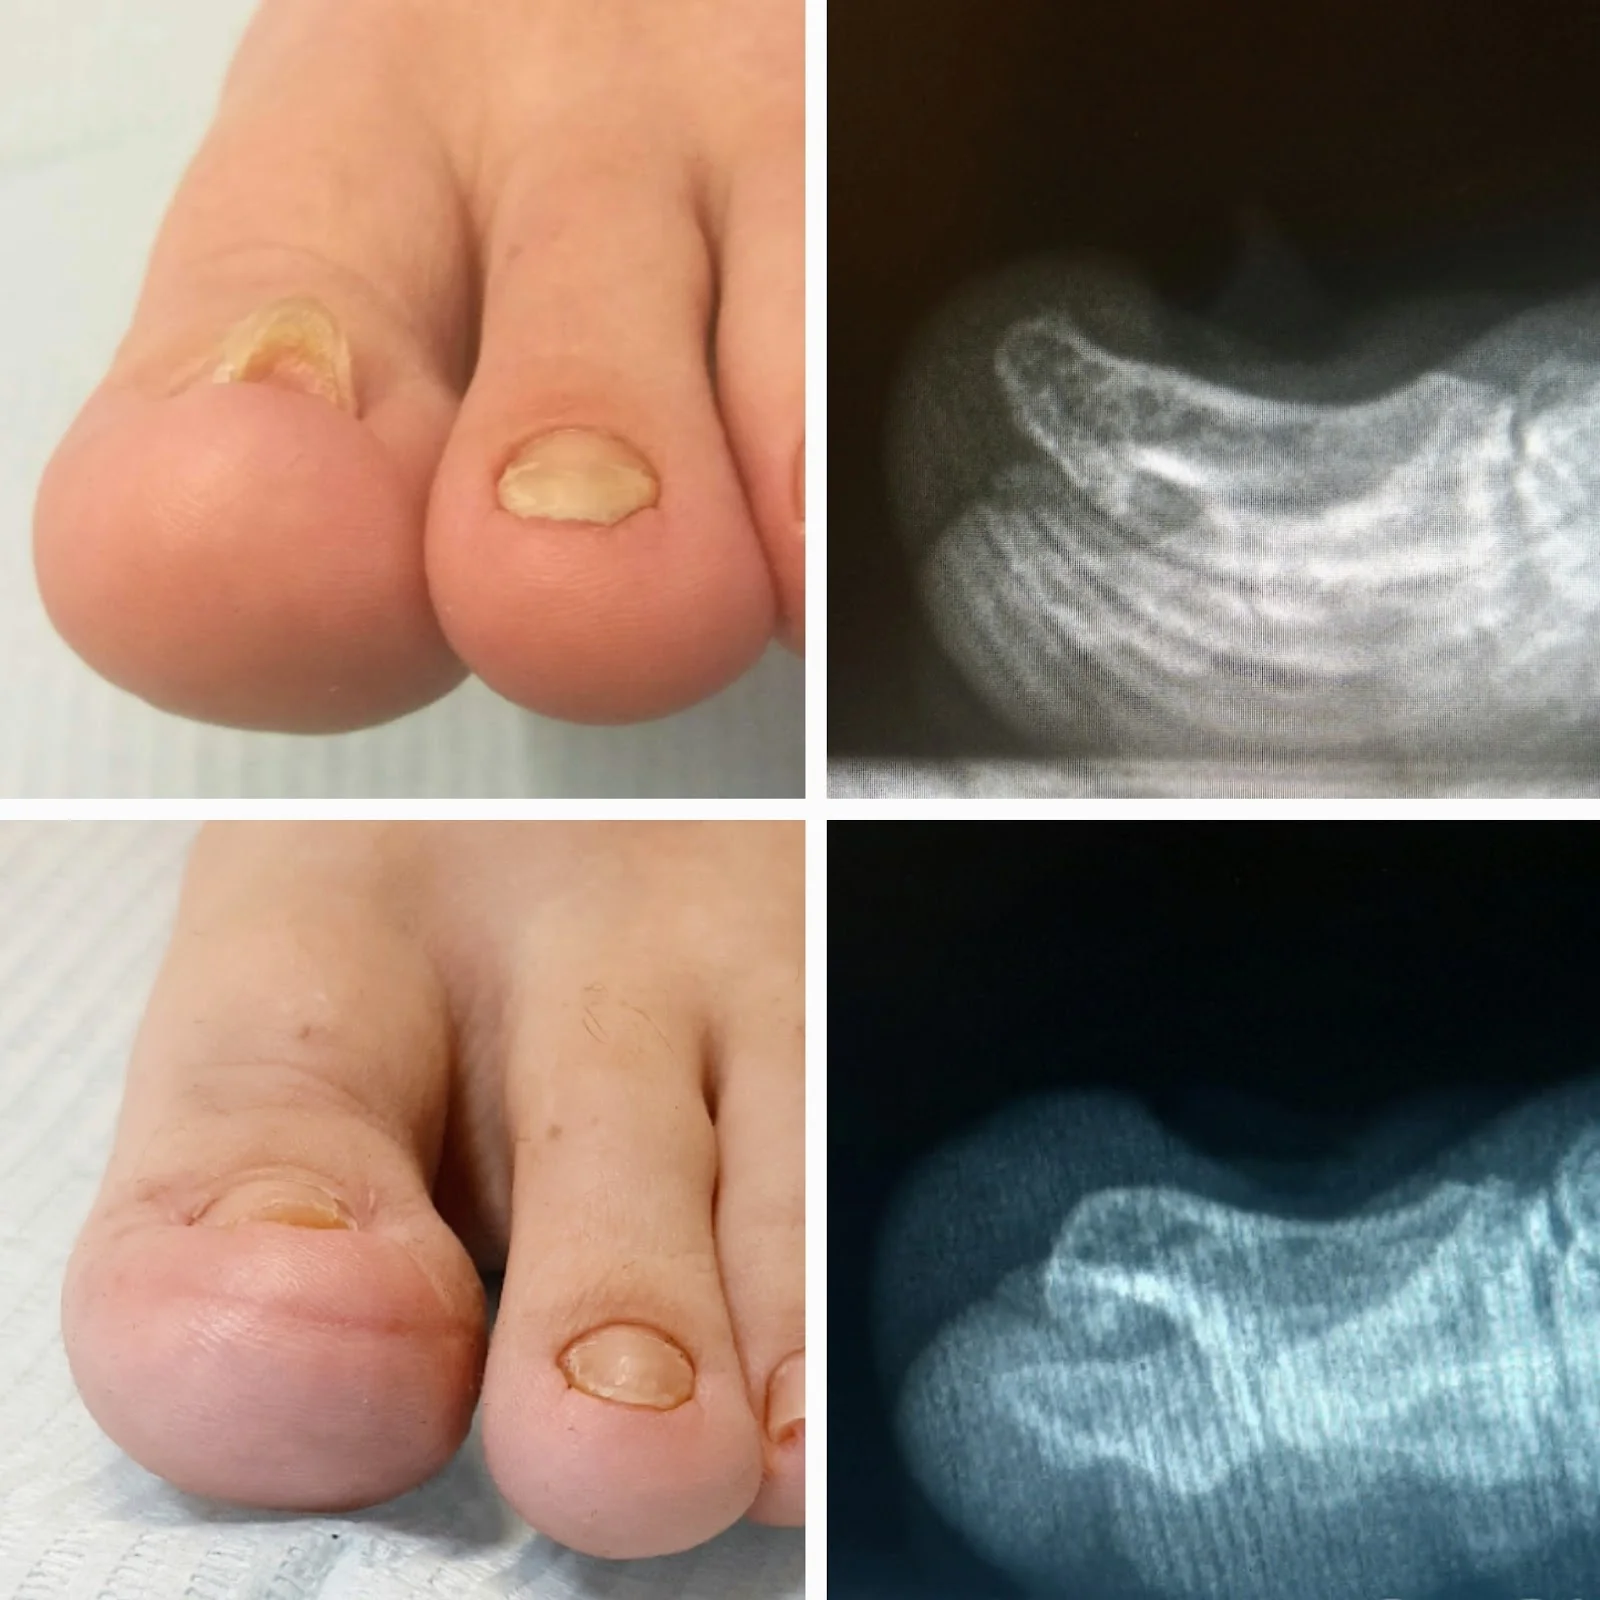

Lo que hace única a la Clínica Lladó es su enfoque en tratamientos precisos de podólogo, desde revisiones rutinarias hasta intervenciones para callosidades, uñas encarnadas y dolor plantar. Los especialistas utilizan equipo moderno para diagnósticos rápidos y terapias efectivas, siempre adaptadas a tus necesidades. Con un precio moderado, obtienes calidad sin complicaciones, ideal para quienes caminan mucho por las playas y senderos de Campos.

Entre los servicios destacados están las sesiones de fußpflege o cuidado podal integral, limpiezas profundas, ortesis personalizadas y prevención de lesiones deportivas. Aunque no se detallan ofertas específicas, la clínica ofrece consultas iniciales exhaustivas y planes de mantenimiento para diabéticos o atletas. Todo a un ritmo que respeta tu agenda, con citas flexibles en esta zona rural de las Islas Baleares.